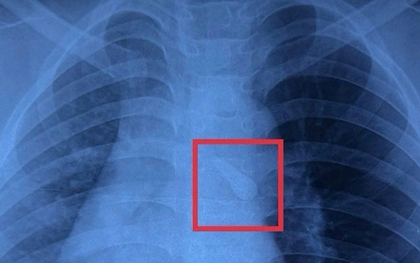

Gắp răng trong đường thở, cứu bé trai 10 tuổi sau tai nạn

Tai nạn giao thông khiến bé trai 10 tuổi bị gãy răng và hít sặc vào khí quản. Các bác sĩ Bệnh viện Nhi đồng 1 (TP Hồ Chí Minh) đã phẫu thuật nội soi kịp thời, giúp trẻ qua nguy hiểm.